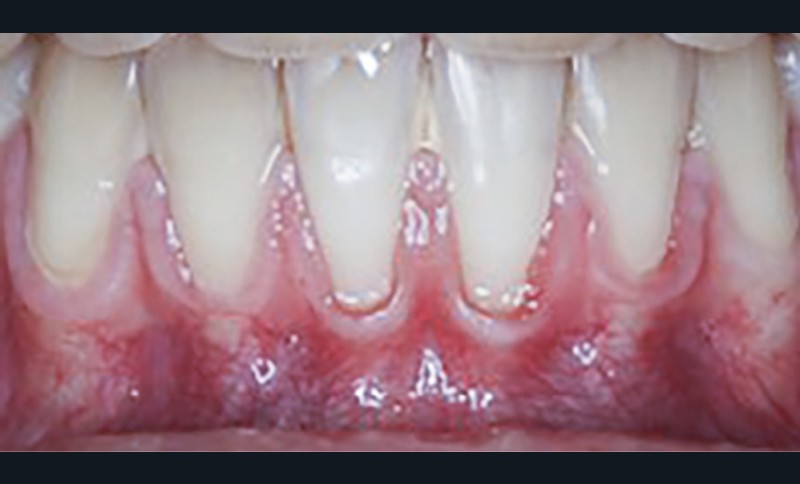

La greffe épithélio-conjonctive (GEC) [7, 8] consiste au remplacement du tissu parodontal existant par un greffon épithélio-conjonctif dont l’indication principale est l’augmentation en hauteur et en épaisseur du tissu kératinisé (fig. 2). Elle peut aussi être utilisée dans le recouvrement radiculaire (avec des résultats en termes de recouvrement inférieurs à ceux des techniques de greffe de conjonctif enfouie), l’aménagement des crêtes édentées, l’aménagement péri-implantaires [9, 10] (fig. 3), ou en association avec un traitement ortho-parodontal [11]. Le principal défaut de cette technique est son aspect inesthétique ; elle sera donc réservée à des zones non visibles comme les incisives mandibulaires ou les zones postérieures.

Les greffes de tissu conjonctif consistent en l’insertion d’un greffon de tissu conjonctif prélevé dans la cavité buccale, sous un lambeau déplacé (avec ou sans décharges), une enveloppe ou un tunnel. C’est la technique de choix pour le recouvrement radiculaire [13], que ce soit pour des récessions unitaires ou multiples, mais elle est aussi indiquée dans l’augmentation en épaisseur des parodontes fins avant traitements prothétiques, orthodontiques ou implantaires.

De nombreuses techniques de lambeaux déplacés latéralement, lambeaux déplacés coronairement (fig. 4), enveloppes ou tunnels (fig. 5) ont fait l’objet de publications et présentent des résultats quasi identiques en termes de recouvrement. Leurs points communs sont un recouvrement complet du greffon, une dissection en épaisseur partielle suffisante pour assurer un positionnement du lambeau sans tension et l’absence (quand cela est possible) d’incision de décharge. Le choix d’une ou l’autre technique dépend surtout de l’expérience du praticien et de la quantité de tissu disponible apicalement ou latéralement.